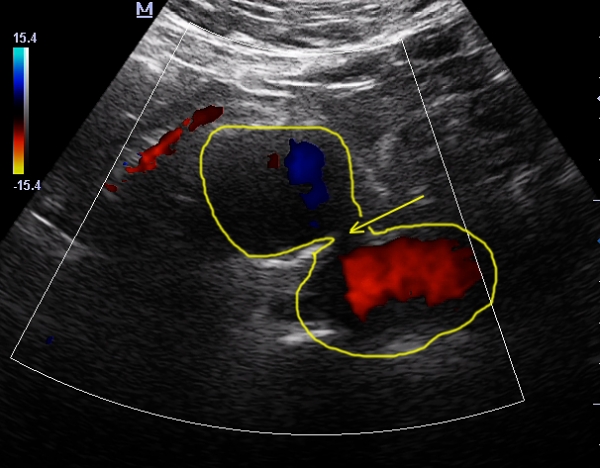

Вообще похоже на расслаивающуюся аневризму брюшного отдела аорты. Если уже на 90% расслоившуюся.

Михаил, вы считаете что это не убедительно смотрится?

Тогда что это по вашему?

Во-вторых глумиться не буду, но мнение Михаила мне как-то ближе...

Что бы такое расслоение? Не уверен!

Извитость, атеросклеротической аорты да неравномерной по диаметру да в разных местах аневризматически расширенной, но опять же неравномерно описала бы увиденную картину в более спокойных тонах!

то что вы тут усиленно рисуете - ложный канал в тромбе